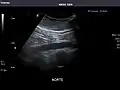

Standard measurement of the abdominal aorta[4]

It can be used on the abdominal aorta to detect or exclude abdominal aortic aneurysm. For this purpose, the standard aortic measurement for abdominal aortic aneurysm is between the outer margins of the aortic wall.[4]